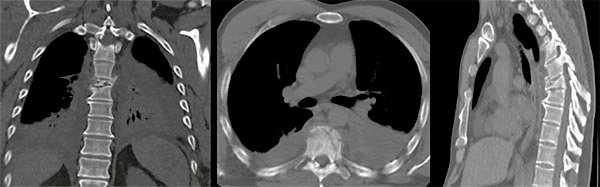

Figura 4:

Caso 8. Hombre de 52 años, accidente vehicular de alta energía cinética. Fractura cerrada de antebrazo, síndrome de distrés respiratorio, hemotórax bilateral, hematocrito en descenso. Se diagnostico una fractura A4 de T8 con mínimo compromiso del canal espinal, posición en cifosis y hemotórax bilateral a predominio izquierdo.

Figura 5:

Caso 8. Se realizó una estabilización percutánea T6-T10. El paciente retornó a UTI, para estabilizar su cuadro respiratorio y hemodinámico.

Figura 6:

Caso 8. A la semana de la primer cirugía el paciente se encontraba en condiciones y se realizó la corpectomía por via lateral MIS.